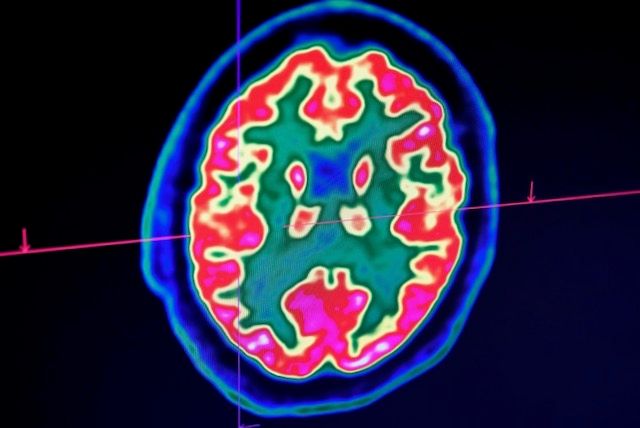

A paper in the New England Journal of Medicine this week examining 58 patients in Strasbourg, France found that more than half were confused or agitated, with brain imaging suggesting inflammation.

The man developed confusion and seizures, and imaging showed his brain was inflamed. But since this is the only known case so far, and the virus test hasn't yet been validated for spinal fluid, scientists remain cautious.

Her team is documenting striking cases including seizures in COVID-19 patients with no prior history of the episodes, and "unique" new patterns of tiny brain hemorrhages.

One startling finding concerns the case of a man in his fifties whose white matter -- the parts of the brain that connect brain cells to each other -- was so severely damaged it "would basically render him in a state of profound brain damage," she said.

Brain imaging and spinal taps are difficult to perform on patients on ventilators, and since most die, the full extent of neurologic injury isn't yet known.